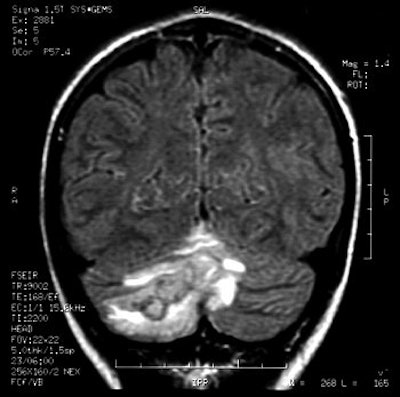

"As the popularity of body art grows, frequency and spectrum of piercing-site infections may increase. Physicians need to consider piercing sites as a source for potential distant infections," wrote Martinello and Cooney in an abstract for the 2001 Infectious Diseases Society of America conference. Images courtesy of Dr Richard Martinello.